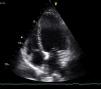

The bedside echocardiogram in the emergency department showed left ventricular dilatation (60/44 mm) with diffuse hypocontractility, more marked in the apex, moderately impaired global systolic function (fractional shortening 26%), but no valvular abnormalities or pericardial effusion (Figure 3). A high-resolution thoracic computed tomography (CT) scan showed a low probability of pulmonary embolism. Serological tests for infectious agents commonly found in myocarditis and Chagas disease were negative.

With a provisional diagnosis of HF of unknown etiology and hypocalcemia secondary to idiopathic hypoparathyroidism, the patient continued the above medication, to which were added intravenous calcium carbonate, a phosphate-binding agent (sevelamer) and vitamin D. Progressive normalization of calcium–phosphate metabolism was observed, accompanied by complete reversal of HF symptoms and normalization of ECG and echocardiographic findings (left ventricular size 50/32 mm, no wall motion abnormalities and fractional shortening 36%). Therapy for hypoparathyroidism was maintained but diuretics, nitrates and ACE inhibitors were discontinued. The patient remained asymptomatic.